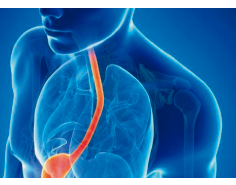

Cirugía Antirreflujo

El reflujo gastroesofágico es el retorno del contenido del estómago hacia el esófago produciendo diferentes síntomas.

- Reflujo

- Sensación de quemadura

- Dolor torácico

- Nauseas

- Eructos

- Tos crónica

- Asma

- Ronquera

Este tipo de cirugía se realiza mediante laparoscopía; es decir, a través de pequeñas incisiones se realiza la reparación de la Hernia Hiatal y se realizan una serie de suturas que permiten que el estómago quede rodeando al esófago, generando una especie de válvula que impide el retorno del contenido gástrico al esófago. Al ser una cirugía de mínima invasión permite que el paciente reinicie dieta el día de la cirugía, tenga mínimo dolor postoperatorio, bajo riesgo de complicaciones de las heridas quirúrgicas y se incorpore de forma temprana a sus actividades.